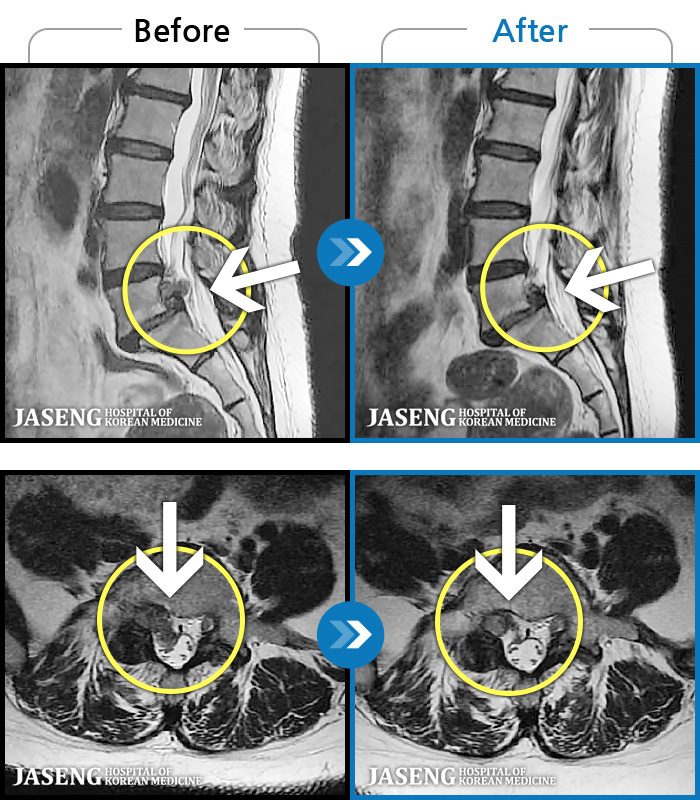

허리통증이 심해서 숙이기 어렵고 차에서 내리기 힘들었습니다.

2021.01.06 ~ 2025.03.10